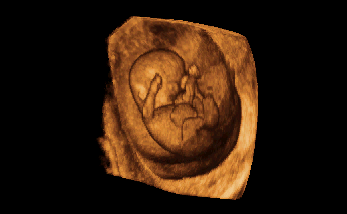

3-D / 4-D Ultraschall

Beeindruckend ist die dreidimensionale Darstellung in der Schwangerschaft, besonders wenn die Bewegungen des Babys zusätzlich "live" gesehen werden können (4-D). Dies gibt Ihnen als werdende Mutter einen ersten Blick auf ihr Kind und damit Sicherheit und Beruhigung.

Nebenan sehen Sie Beispiele für die dreidimensionale Darstellung